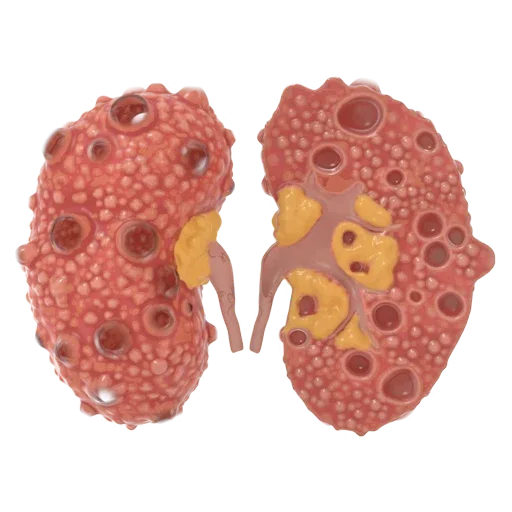

Polycystic Kidney Disease

Polycystic Kidney Disease: Natural Treatment and Management with Medilux Lifecare Polycystic Kidney Disease (PKD) is